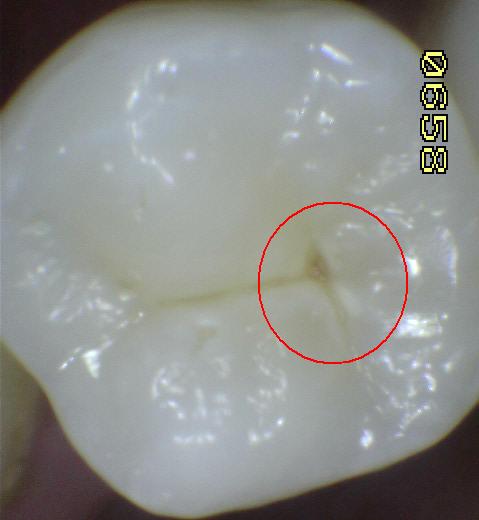

Código 4: Sombra oscura

de dentina subyacente, con o sin interrupción localizada del

esmalte

- Esta lesión aparece como una

sombra de decoloración visible a través de una superficie de

esmalte aparentemente intacta, la que puede o no mostrar

signos de descomposición localizada < 0,5mm. en

esmalte, al secado con aire.

- La aparición de la sombra oscura de dentina, se ve a menudo con

más facilidad cuando el diente está húmedo.

- El área oscura es una sombra intrínseca que puede aparecer gris, negro-azul o

anaranjado-marrón.

- La sombra clara debe representar a la caries que se inicio en

la superficie del diente que se está evaluando. Si a juicio del

examinador, la lesión de caries empezó en una superficie adyacente y no

había ninguna evidencia de caries en la superficie, a continuación esa

superficie se

anota como código 0

- Los códigos 3 y 4, histológicamente puede variar en profundidad, uno

puede ser más profundo que el otro y viceversa.